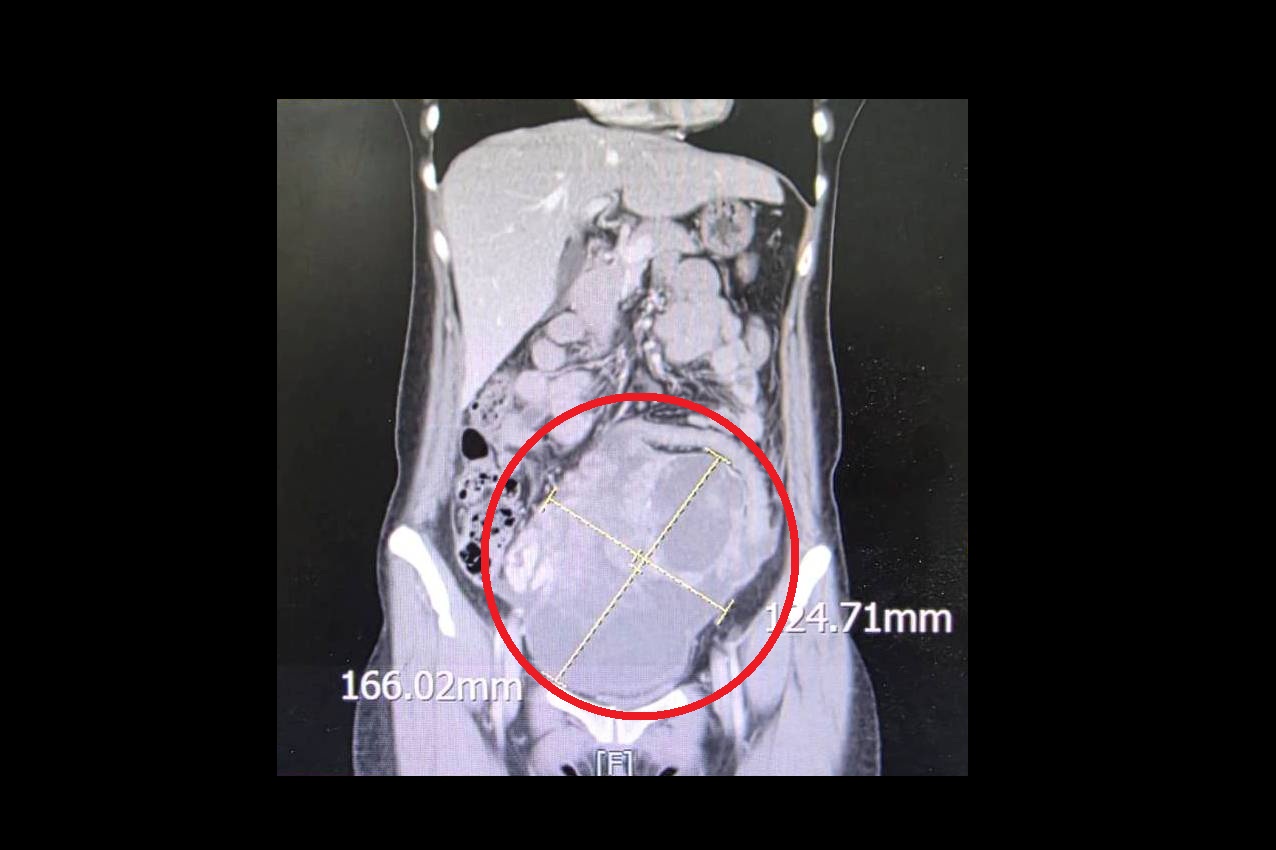

病人就醫發現腹部直徑高達16公分的巨大腫瘤(紅圈處),病理報告為罕見的同步性子宮內膜

一名44歲未婚女性,持續兩週感到腹痛、腹脹且食慾不振,原以為是腸胃不適,就醫檢查後竟在腹部發現直徑高達 16公分的巨大腫瘤,且癌症指數(CA-125)飆升至 900 U/ml(正常值為 <35 U/ml)。大千綜合醫院婦產科劉榮啟醫師緊急安排手術切除子宮及兩側卵巢,術後病理報告證實為罕見的「同步性子宮內膜癌與卵巢癌(SEOC)」。在醫療團隊悉心治療下,病人至今已成功抗癌滿5年,復原狀況良好。